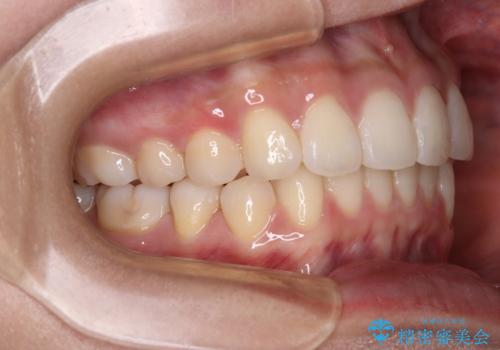

- 前歯のデコボコを治したいとのことで来院された患者様です。

上下顎ともに歯列全体の後方移動とIPR(歯と歯の間を削る)によってデコボコが解消するように設計し、インビザラインにより治療を行うこととしました。

上下ともにIPRを積極的に行っているため、舌の突出癖をしっかりと改善できないと、後戻りにより隙間やデコボコが早い段階で発現することになるため、舌のトレーニングが非常に大切になります。